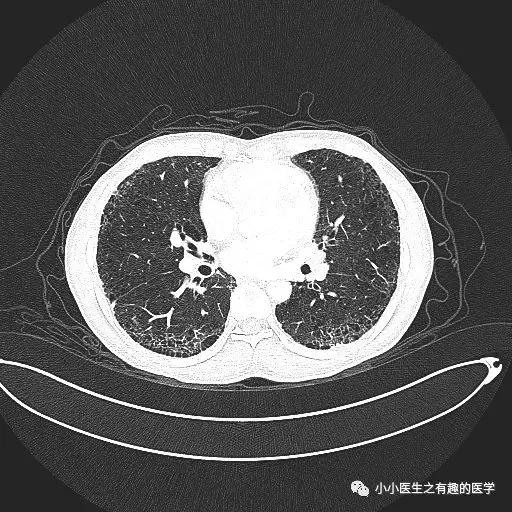

间质性肺炎的影像学表现,复杂的很复杂,有时候和肺炎不容易区分。

经典的间质性肺炎,就是一张网!

1.胸膜下2.网格状很多间质性肺炎,都有这个特征,是间质性肺炎的入门知识,也是很重要的知识。